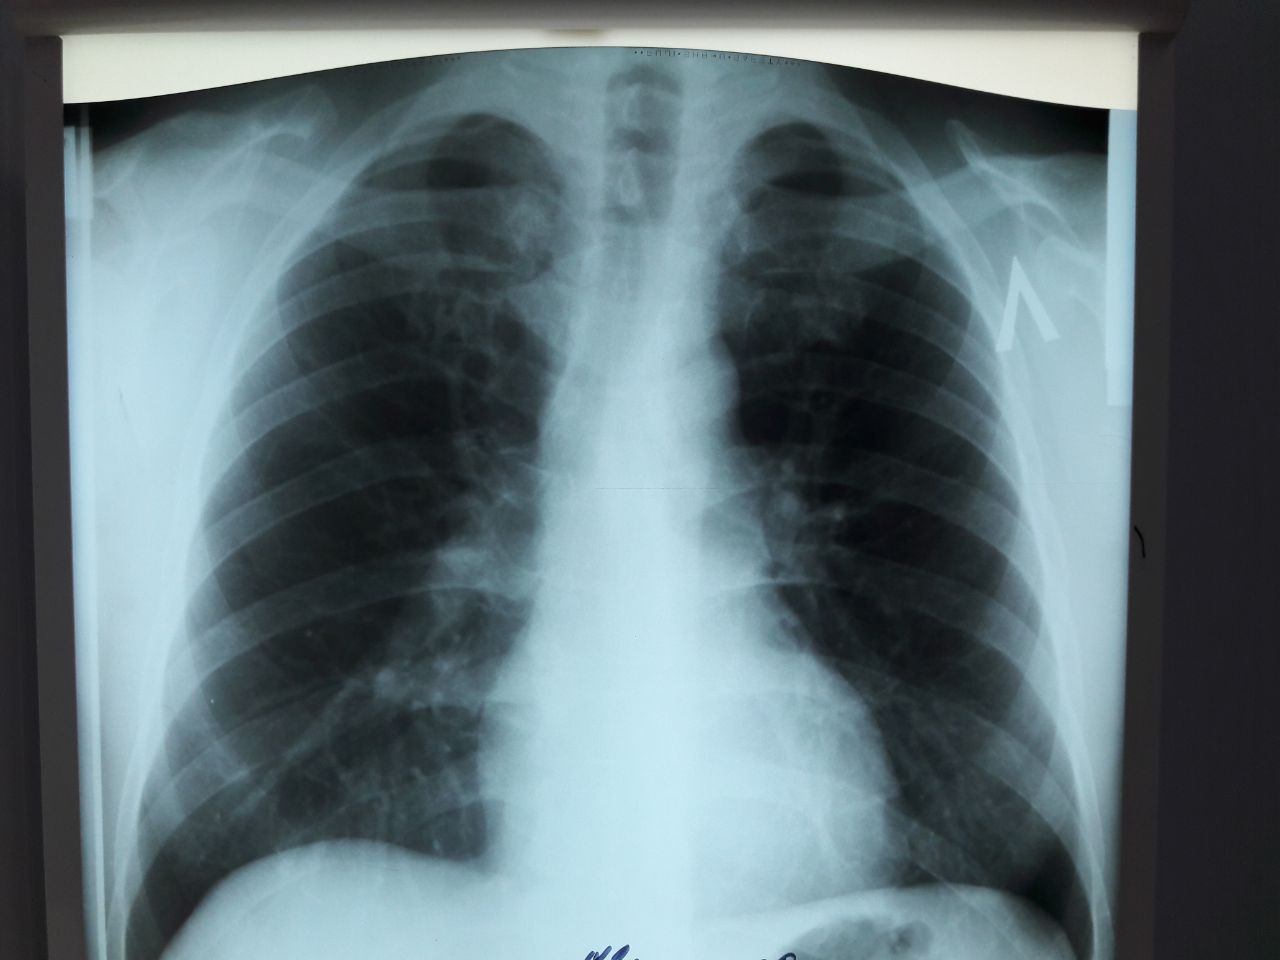

здравствуйте, жалоб нет , но не нравиться вот эта тень , что может быть ?

Трахея

контуры ровные

Грудина